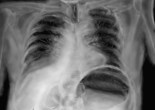

Dilatation aiguë de l’estomac, volvulus gastrique